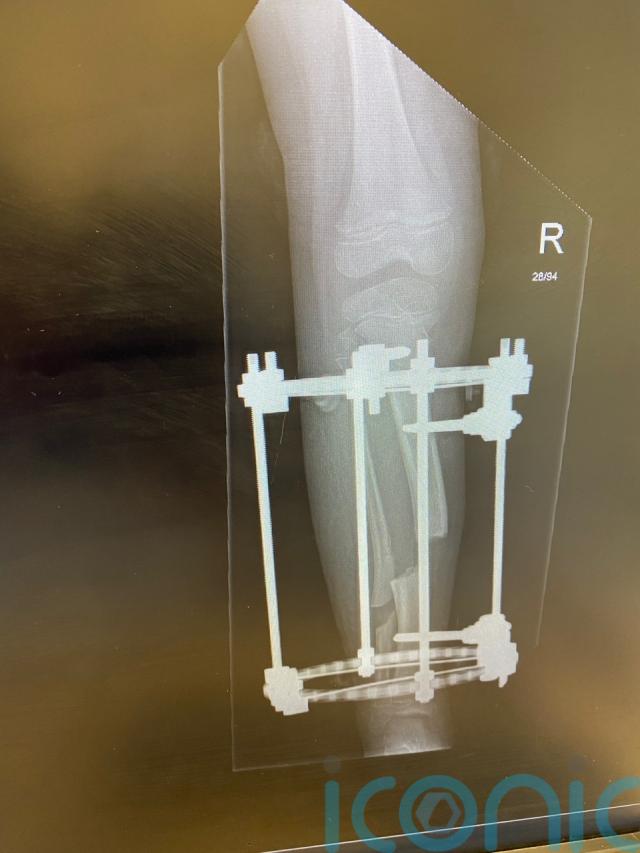

He was referred to Mr Jabbar in September 2018 and underwent an operation in April 2019 which saw a frame fixed to his leg with the aim of stretching the tissues in his knee.

An ultrasound identified a large collection of fluid and medics discovered one of the pins used to secure the frame had protruded into Mr Wood’s thigh.

When it was removed, there was a lot of bleeding and surgeons noted damage to his femoral artery.

The frame was removed and Mr Wood was then placed in a permanent full-length leg cast to support his leg.

An independent review for Gosh into his treatment found “poor surgical skill” by Mr Jabbar had resulted in a pin going into Mr Wood’s thigh when the frame was fitted.

It said the type of pins used had increased the risk of vascular injury and other pins should have been used.